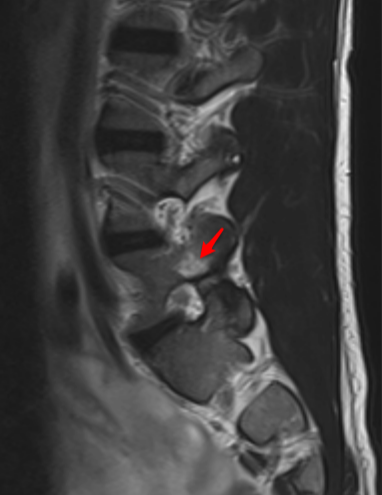

Pars interarticularis stress response